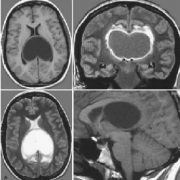

三分之二的患者存在脑积水,60%-75%的患者在出现症状时或初次治疗后不久就需要进行脑脊液分流手术。Rutka教授的丘脑胶质瘤治疗案例CT及MRI显示右侧丘脑...